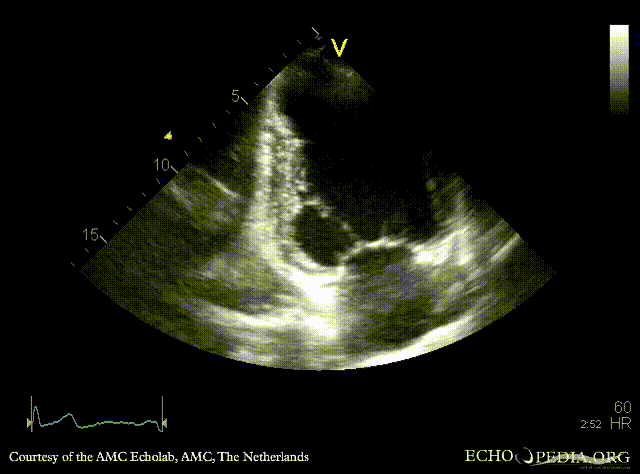

Apical aneurysm of LV

PLAX: dilated left ventricle, apical aneurysm PSAX: dilated left ventricle, reduced function